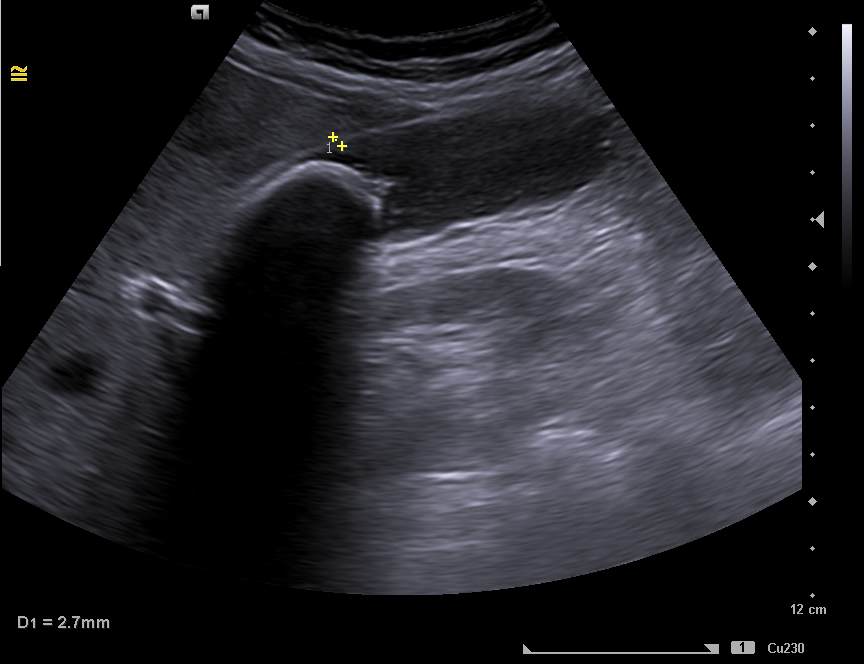

Ante la clínica se cita a la paciente en ayunas, para conseguir una máxima distensión de la vesícula.  Se observa una imagen hiperecogénica  móvil, con sombra acústica posterior compatible con litiasis de 35 mm. Sin colección perivesicular ni dilatación de la vía biliar intrahepática y extrahepática. Hígado con ecoestructura y ecogenicidad normal, sin LOES en su interior.  Hallazgos compatibles con litiasis vesicular gigante, descartando el diagnóstico de vesícula en porcelana.